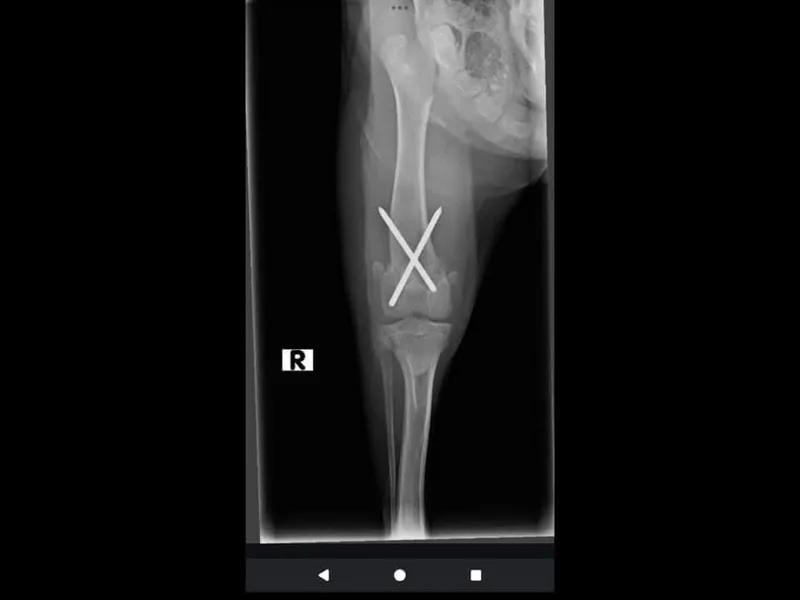

Say Hello to Willowby! She is a 6 month old, brindle girl who is ready for her forever home! Unsure of breed, but will likely be a medium-large sized girl! Right now at six months old she weighs 21 pounds. Willowby had a broken back leg when she came into the rescue, First stop was Siouxland animal Hospital. After extensive surgery and having two pins put in she is now healed!  Thank you Dr. Samuelson for your amazing work. At first, she was in a lot of pain and couldn't use her back leg, but now it is all good to go with no problems! She runs, plays, jumps, and wrestles like it was never broken! She may have some arthritis later on in life. But that can easily be monitored with pain meds. Willowby is a puppy and will need continued training, but she is such a quick learner, already knows sit and is kennel trained. Potty training is also going very well! She only ever has an accident if she gets too excited! Willowby gets along with all dogs, loves to initiate play, but also needs those puppy naps and enjoys cuddling too! She loves children and all humans! Kisses are never ending with her and she has found her voice to let you know how excited she is to see you! If you are looking for the perfect mix of puppy love and a loyal companion, trainable girl who only deserves the best, Willowby is your girl! She is spayed, microchip, and up-to-date on vaccinations. If interested, please click the link below for an adoption application. Adoption fee is 135. https://form.jotform.com/50308432400137